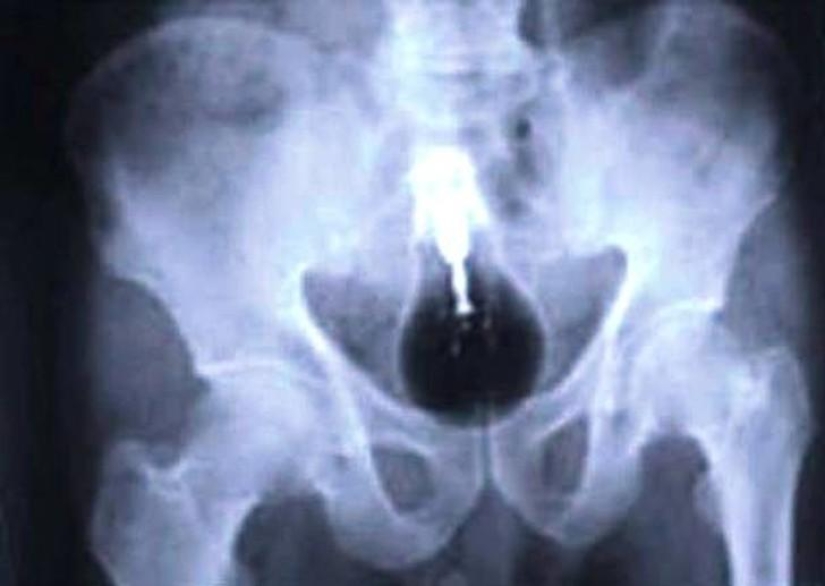

Bullet.